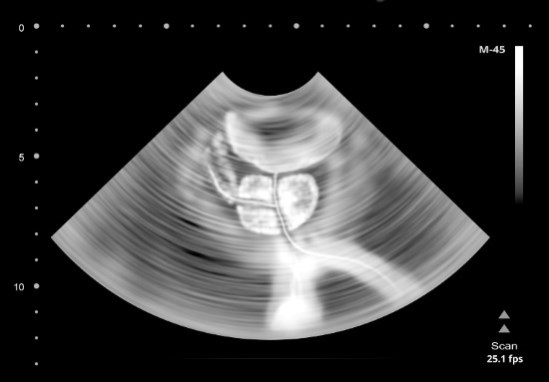

Увеличенная простата может блокировать прохождение мочи в мочеиспускательном канале и усиливать позывы к мочеиспусканию.

Эта выводная трубка мочевыделительной системы выходит из самой низкой точки мочевого пузыря, что позволяет избежать застоя мочи. Длина мочеиспускательного канала у женщин составляет около 4 см. Он расположен между клитором и влагалищем и выполняет единственную функцию – выведение мочи. У мужчин же мочеиспускательный канал может быть длиной около 20 см. Он проходит через предстательную железу (простату), расположенную под мочевым пузырем, и выходит наружу в половом члене. К счастью, эякуляция и мочеиспускание не могут происходить одновременно. Поскольку простата и мочевая система мужчин тесно связаны, частое мочеиспускание или слабая струя мочи часто являются ранним признаком увеличения простаты. В более тяжелых случаях, когда отверстие мочеиспускательного канала полностью перекрывается, требуется срочное медицинское вмешательство, поскольку этот симптом может привести к различным патологиям мочевыводящих путей.